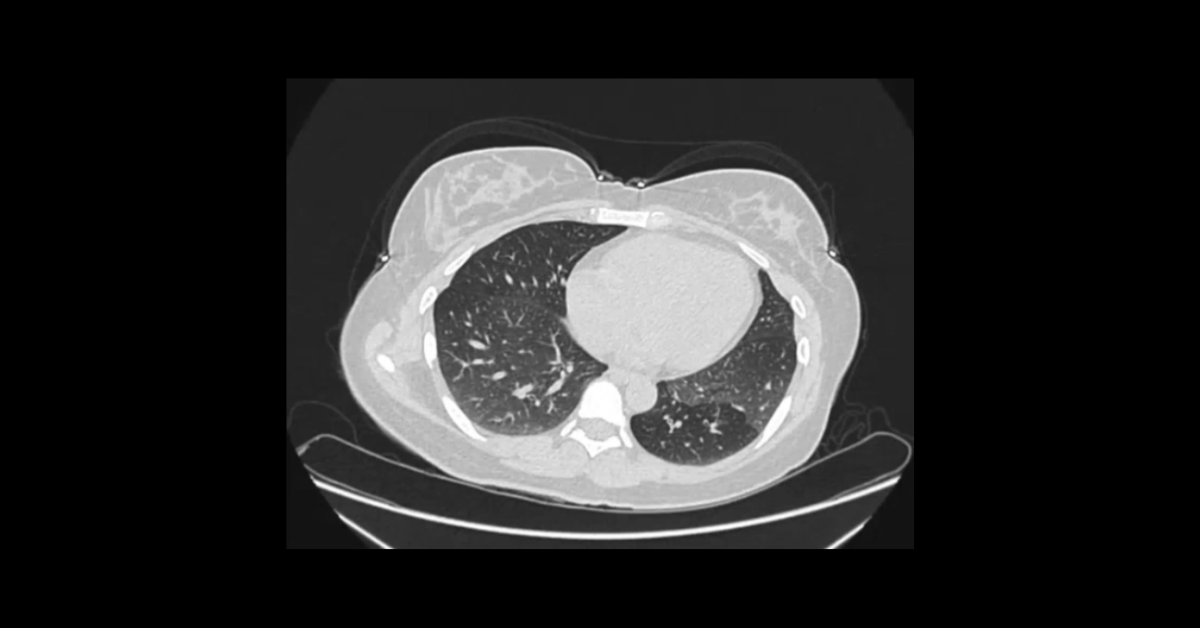

Presented by Vincent Mellnick, MD at Practical Radiology 2025. The upper gastrointestinal tract can be oft-overlooked site of disease in the emergency department patient, but is frequently be the site of pathology, including inflammation/infection, ischemia, obstruction, perforation, and hemorrhage. This talk will discuss common (and some uncommon) conditions causing these presentations in the esophagus, stomach, and duodenum, with emphasis on CT findings.